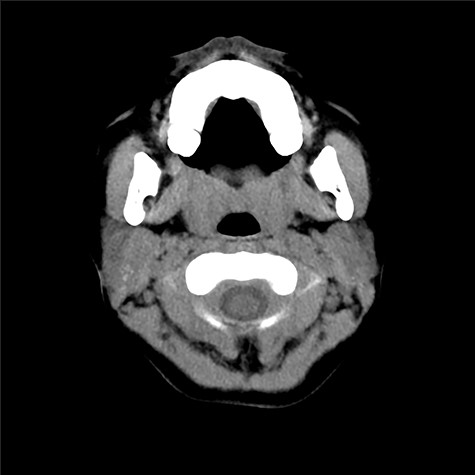

An 8-year-old Japanese girl was introduced to our department from an ear-nose-throat doctor, with a diagnosis of infected epidermal cyst. She had a subcutaneous induration with a diameter of 5 × 12 mm, below the right mandibular angle (Fig. 1). Recurrent inflammation had been persisting for a year. Pediatrist had followed her with a diagnosis of recurrent parotitis. Previously, CT (Fig. 2) and MRI images had been taken and the radiologist found small calcifications in her right parotid gland but no sign of parotitis, cysts or fistula. No other abnormality, including extra auricular canal, was detected. No particular family history was recorded.

CT scan taken prior to the first visit. There can be seen subcutaneous induration, but no cysts nor fistula was obvious.